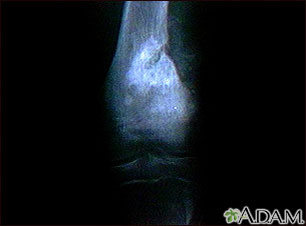

A bone x-ray is an imaging test to look at the bones.

A bone x-ray is used to look for injuries or conditions affecting the bone.

Abnormal findings include:

- Fractures or broken bone

- Bone tumors

- Degenerative bone conditions

- Osteomyelitis (bone infection)

- Arthritis